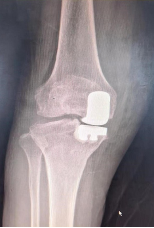

适用于晚期关节屈伸活动严重受限、畸形、生活不能自理的患者。人工关节置换术分全膝置换术和部分膝关节置换术,目前部分膝关节置换术中较为成熟的有单髁置换术。

全膝置换术:是治疗膝关节骨性关节炎的金标准,可以有效消除或缓解疼痛症状,改善患者运动功能,矫正患肢力线,提高患者生活质量。但是全膝置换术切除了前后交叉韧带、半月板,手术创伤大,术中出血量大,术后恢复慢,膝关节功能不完善,并且全膝置换术属于终极手术,截骨量多,术后翻修困难。

(全膝置换术后影像)